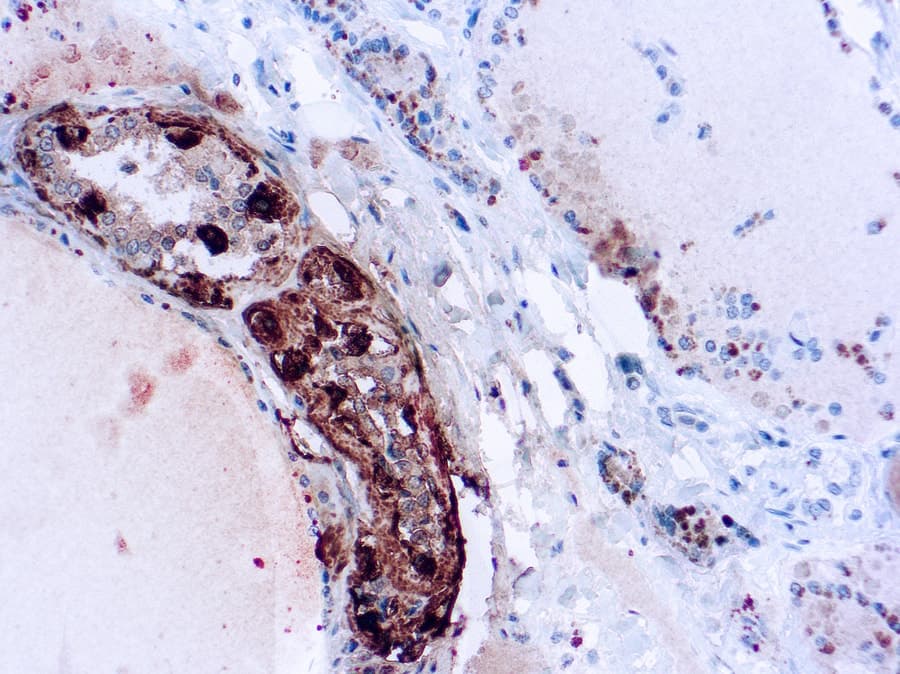

Coupe de carcinome médullaire de la thyroïde

Coupe de carcinome médullaire de la thyroïde